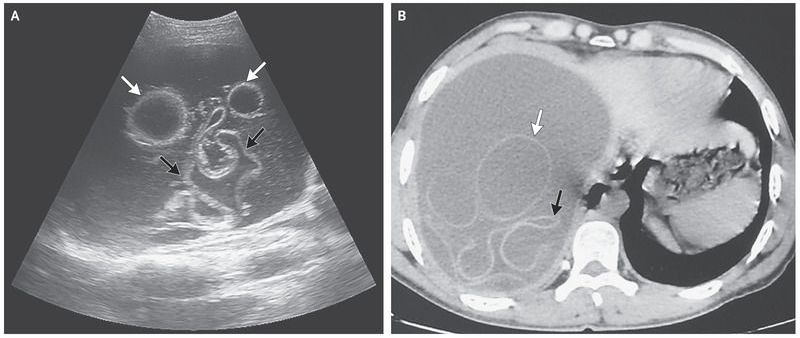

A 30-year-old man presented with a 15-month history of intermittent discomfort in the right upper quadrant of the abdomen. He lived in a rural area of Morocco and had occasional contact with dogs. The physical examination revealed hepatomegaly with a palpable hepatic mass. Laboratory tests showed a normal white-cell count and a normal absolute eosinophil count. Ultrasonography (Panel A) and computed tomography (Panel B) of the abdomen revealed a large cyst in the right lobe of the liver, containing hydatid membranes (black arrows) and daughter vesicles (white arrows). An enzyme-linked immunosorbent assay indicated an anti-echinococcus IgG antibody index of 16.7 in the patient’s blood (normal value, ≤11). Hydatid disease is caused by the echinococcus tapeworm. Dogs are the definitive host; the infection is transmitted when eggs shed in their stool are ingested by humans or other animals. The patient underwent laparotomy, during which the cysts were removed in their entirety with no spillage of their contents. Echinococcus granulosis was detected. A follow-up ultrasound examination 2 months after surgery showed no sign of recurrence.